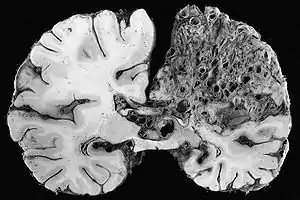

A very large arteriovenous malformation in the left hemisphere (on the right in this image) of the brain.

Arteriovenous malformations (AVMs, larger vascular malformations) occur in larger organs, predominantly the lungs (pulmonary AVMs) (50%), liver (30–70%) and the brain (cerebral AVMs, 10%), with a very small proportion (<1%) of AVMs in the spinal cord.[1][2]

In the brain, AVMs occasionally exert pressure, leading to headaches. They may also increase the risk of seizures, as would any abnormal tissue in the brain. Finally, hemorrhage from an AVM may lead to intracerebral hemorrhage (bleeding into the brain), which causes any of the symptoms of stroke such as weakness in part of the body or difficulty speaking. If the bleeding occurs into the subarachnoid space (subarachnoid hemorrhage), there is usually a severe, sudden headache and decreased level of consciousness and often weakness in part of the body.[1][2]